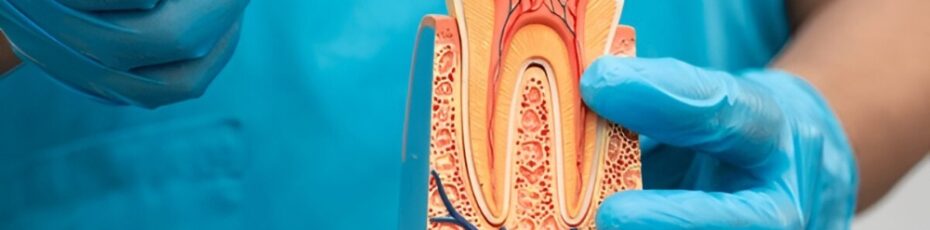

Dealing with a sharp, throbbing ache in your mouth can make it very hard to focus or sleep. When you visit a dentist near you to find a fix, the main goal is to stop the hurting and keep you healthy. While keeping your real teeth is always the first plan, sometimes a tooth is…